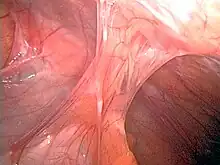

| Adhesions formed following appendectomy |

Adhesions are fibrous bands that form between tissues and organs,[1] often as a result of injury during surgery. They may be thought of as internal scar tissue that connects tissues not normally connected.